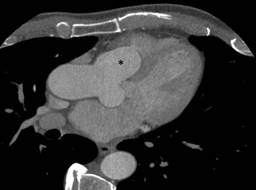

The CT angiography confirmed the echocardiogram findings and suggested a small right coronary artery (RCA), not shown in our Figures, and a normal left anterior descending coronary artery with compression of the right ventricular outflow tract (Figure 3).

Figure 3: A chest computed tomography-sagittal view showing dilation of the aortic root and expansion of the aneurysm (asterisk) into the right ventricle.